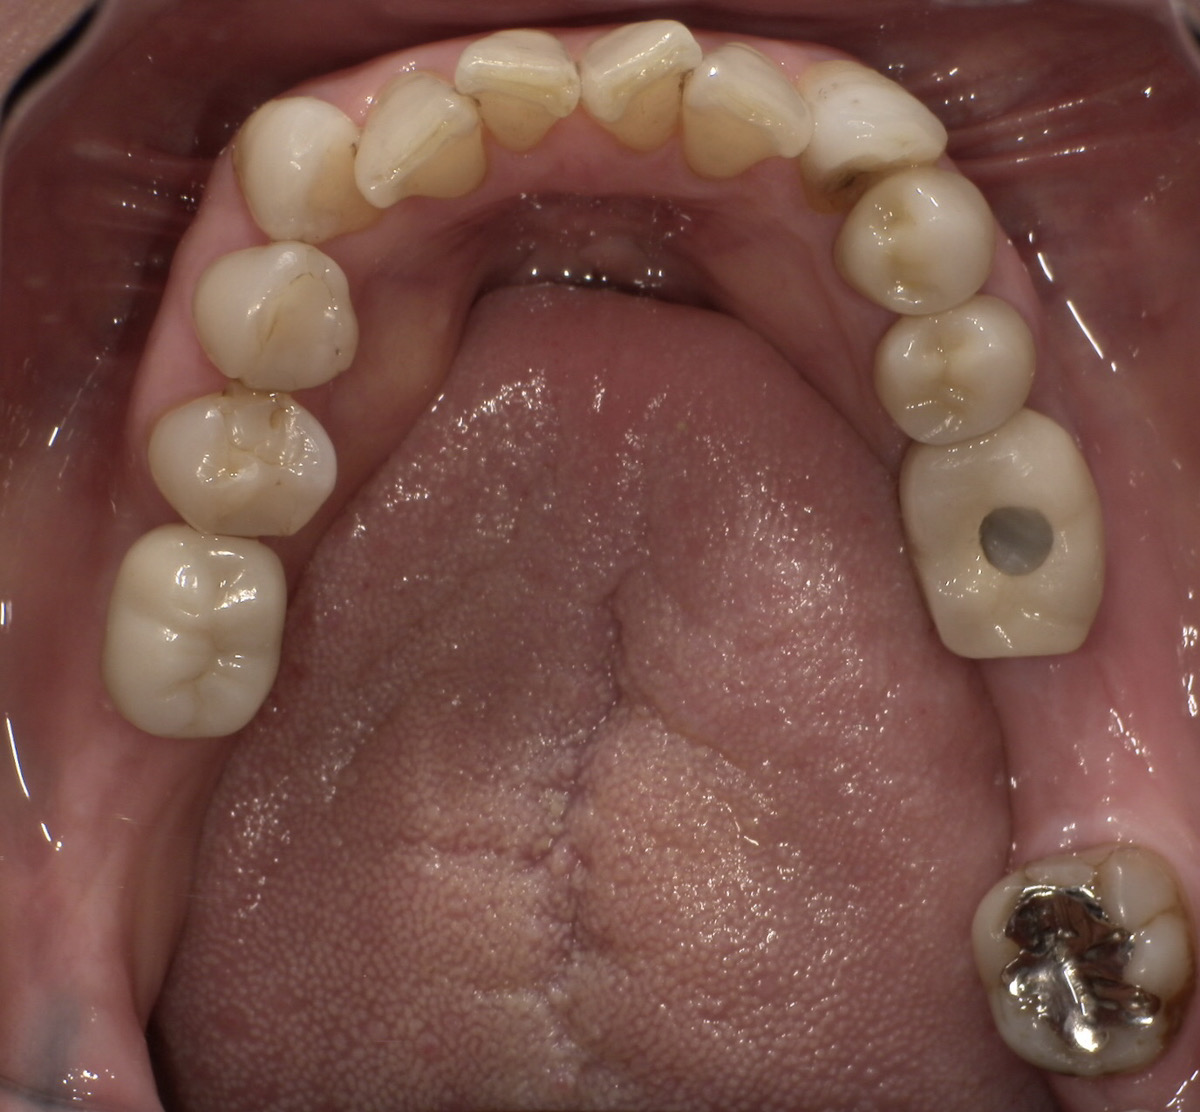

CASE 03

Before

After

施術内容左右下顎の第一・第二大臼歯の銀歯(被せ物)をジルコニアクラウンに交換。右下第二小臼歯の銀歯(詰め物)をジルコニアインレーに交換。

治療期間3か月

リスク・副作用ジルコニアは非常に強度が高いですが、強い衝撃や極端に強い噛み合わせ、歯ぎしり・食いしばりなどがある場合、まれに割れたり欠けたりする可能性があります。

費用 454,400円

※表示金額は全て税込みです。